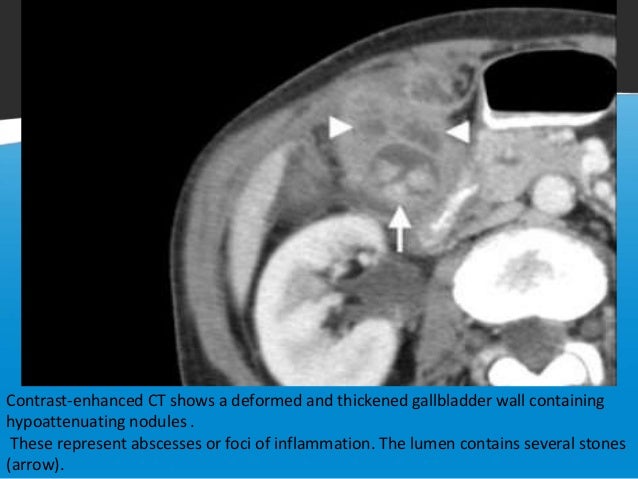

Symptoms of this condition tend to be vague. Bronchial wall thickening ultrasound of liver and gallbladder gallbladder contracted on ultrasound. Wall thickening of gall bladder caused due to obstruction in persistent movement in cystic duct by stones.